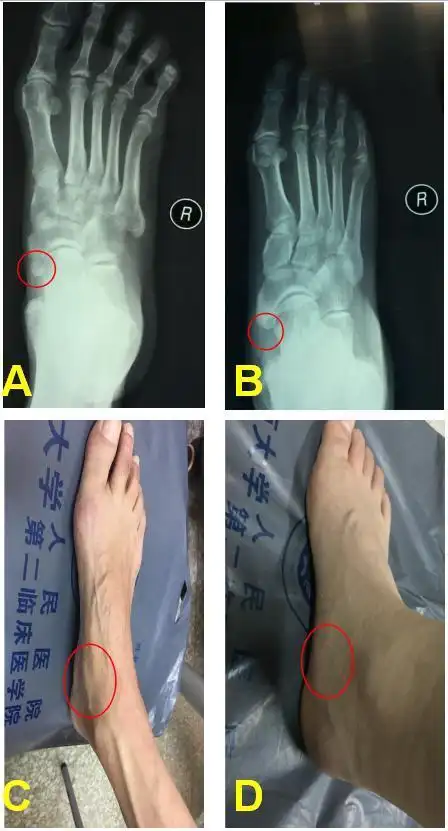

踝关节常见伤病——足副舟骨疼痛

出现足弓内侧疼痛,发红或者淤青,摸起来有一个硬块,这块骨头叫副舟骨

青少年足痛当心副舟骨疼痛

足副舟骨疼痛综合症 - 好大夫在线